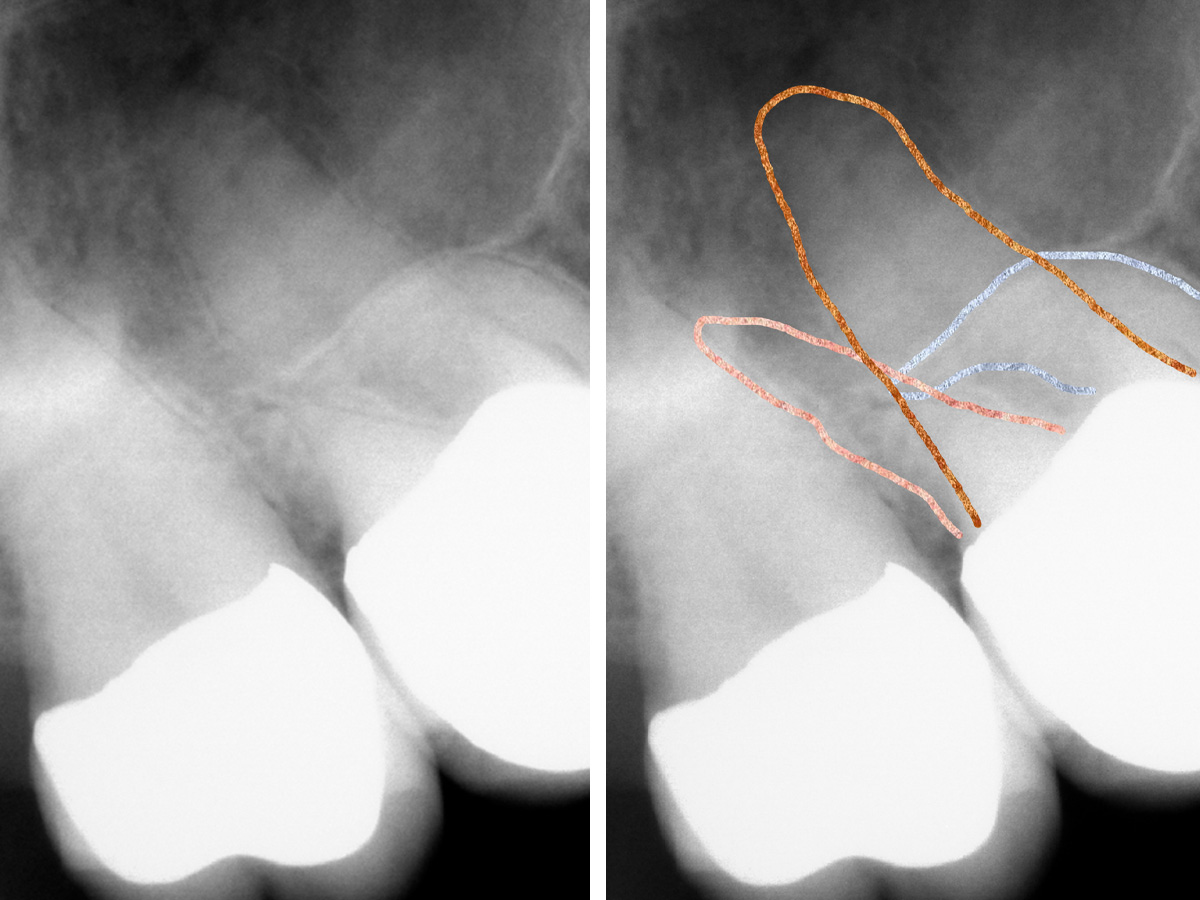

Abbildung 2

Nach der DVT-Untersuchung (Kodak 9000 3D, Auflösung 0,076 mm) bestätigte sich eine apikale Parodontitis an Zahn 16 palatinal. Eine Wurzelkanalbehandlung an Zahn 16 ist indiziert.

Abbildung 3a

Obliterierte bukkale Kanäle...

Abbildung 3b

...und eine starke Krümmung mesiobukkal.